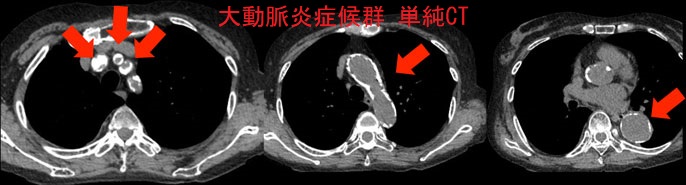

大動脈炎症候群(高安動脈炎、脈なし病)の画像所見は、

- 非造影CT;肥厚した動脈壁が高吸収

大動脈炎症候群 単純CT (東京レントゲンカンファレンス)